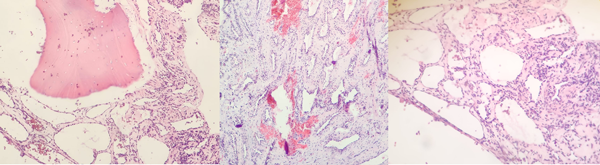

La anatomía patológica informó hemangioma (Figura 4). Se completó el estudio con una angiografía selectiva dorsal (ASD) que reveló una lesión hipervascular con emergencia de la arteria radicular magna de Adamkiewickz a nivel de D7 izquierdo. Se decidió tratamiento mediante embolización tumoral. A los dos meses se efectuó el procedimiento con n-butil-2-cianoacrilato superselectivo embolizando las arterias de los pedículos D8 y D9 bilateral logrando una desvascularización completa de la lesión (Figura 5). A los 4 meses de la cirugía, la RM no mostró progresión de la enfermedad (Figura 6), a los 9 meses, el paciente continúa asintomático, sin déficit motor, sensitivo ni compromiso de esfínteres.

Figura 4. Imágenes de anatomía patológica. Coloración hematoxilina-eosina. Magnificación 10x y 4x. Microscopía: tejido óseo trabecular maduro en cuyos espacios medulares se observa una proliferación vascular benigna, constituida por vasos de pequeño a mediano tamaño, algunos dilatados, revestidos por endotelio sin atipias, con hematíes endoluminales que asientan sobre estroma fibrovascular con hemorragia reciente.